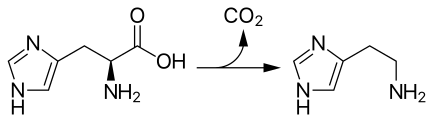

Histamine is derived from the decarboxylation of the amino acid histidine, a reaction catalyzed by the enzyme L-histidine decarboxylase. It is a hydrophilic vasoactive amine.